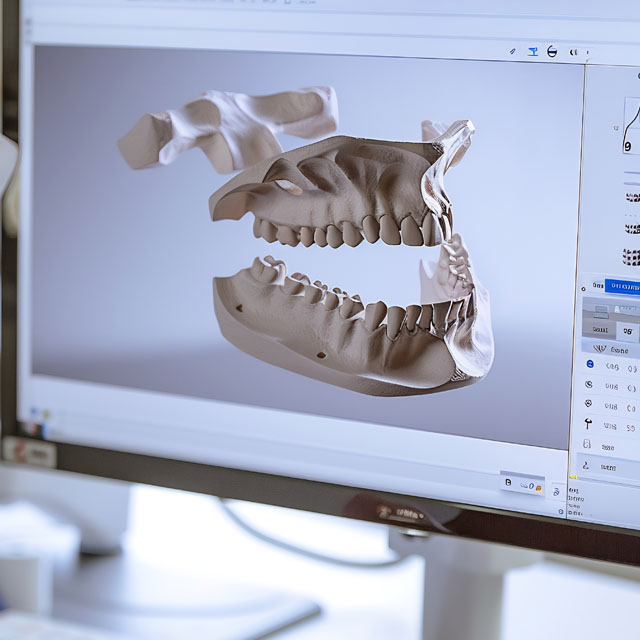

First, our dentists will perform a thorough examination. We may use modern imaging, such as X-rays or a CT scan, to get a clear picture of the growth. The only way to know for sure what a growth is through a biopsy, where a small sample of tissue is taken and analyzed.